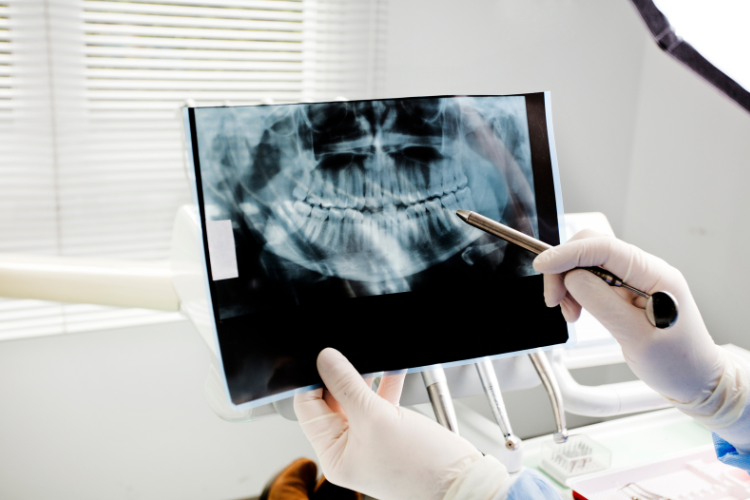

The periodontist evaluates the extent of gum disease through clinical examination, X-rays.